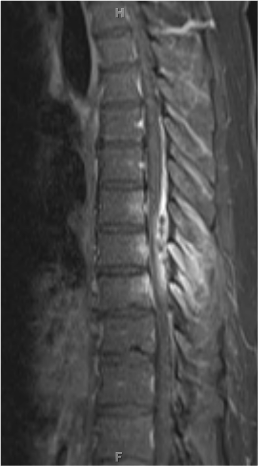

Imaging Approach to Myelopathy: Acute, Subacute, and Chronic